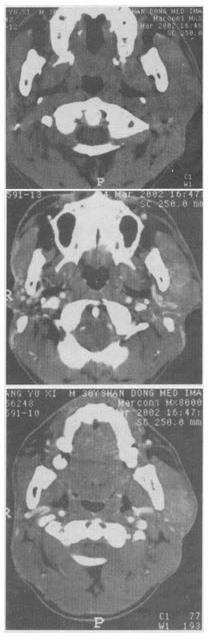

- 单项选择题 女性,45岁。发现左侧腮部肿块1年余,逐渐长大,无明显不适。CT检查如图所示,应首先考虑()。

A、腮腺囊腺淋巴瘤

B、血管瘤

C、脂肪瘤

D、淋巴瘤

E、多形性腺瘤

- E